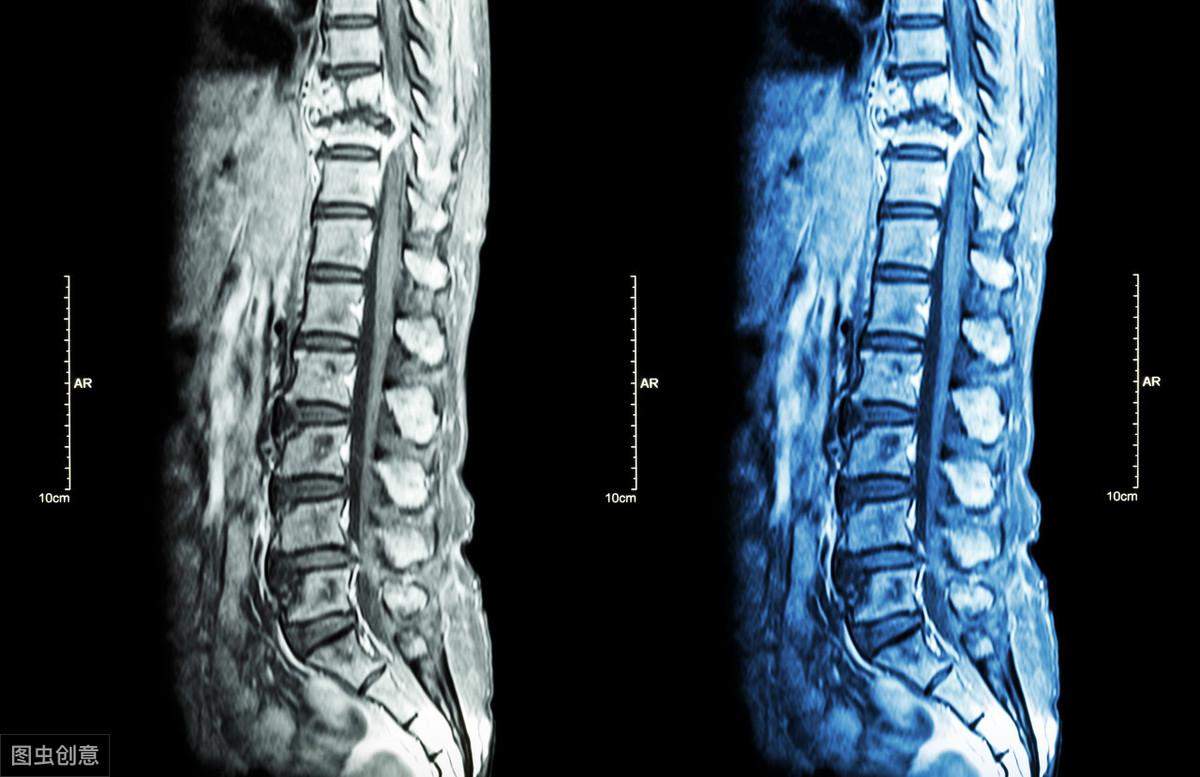

五、强直性脊柱炎是如何诊断呢?

诊断标准:45岁前发病,出现发炎性的下背痛(特征是休息无法缓解)合并晨僵且持续3个月以上。

白细胞表面抗原:抽血检查,用于检测HLA-B27基因。

(1)类风湿性关节炎:多见于女性,主要累及四肢小关节,少数累计脊椎,常为颈椎,骶髂关节很少累计,若受累到本病晚期,常为单侧发病,以骶髂关节韧带部侵犯多见,关节面下骨质疏松,继而出现小囊状骨质破坏。类风湿因子阳性,HLA-B27阴性。(2)致密性骨炎:多见于中青年女性。典型表现为在髂骨沿骶髂关节中下 2/3 部位有明显的骨质硬化,呈三角形者尖端向上,密度均匀,MRI显示髂骨为低信号,关节间隙、骶骨面和关节软骨正常,周围无骨髓水肿。(3)骶髂关节结核:多为单侧发生,常有明显全身症状。骶髂关节骨质破坏,常合并关节周围脓肿。PPT试验阳性,HLA-B27阴性。(4)其他:在诊断时有与骶髂关节炎相关如Reiter综合征、脊椎骨关节炎等,需进一步根据相关临床特征进行区别。